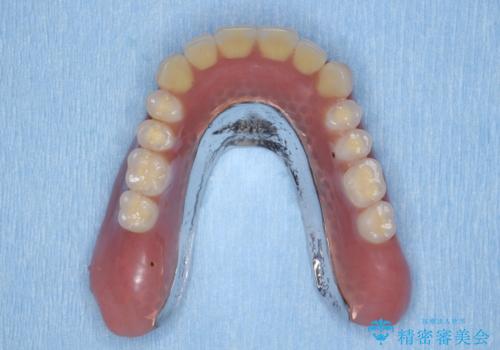

インプラント支台のマグネットを用いることで安定してしっかりと噛めるような総義歯治療を計画します。

- 100万円(インプラント・マグネットアバットメント×3・金属床義歯)費用は治療当時の料金となります

通常の入れ歯は歯ぐきで支えるため話したり食事の際に動いたり安定が悪くなってしまうことが多いですが、インプラント支台のマグネットを設定することでより安定してしっかりと噛むことができるようになります。